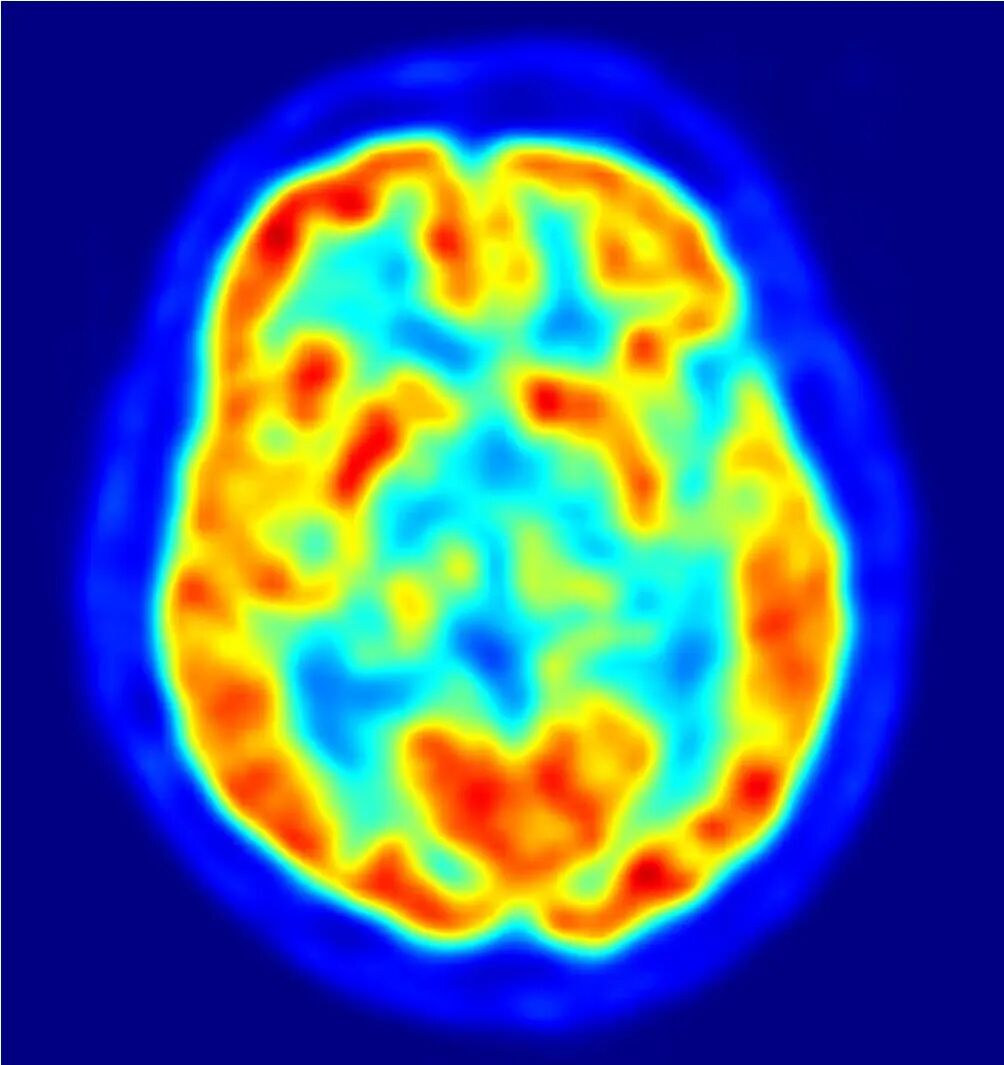

正电子发射断层扫描(PET)

这种核医学成像技术是将一种通过正电子发射衰变的同位素(即B+粒子)注入人体。当这种正电子遇到电子(β粒子)时,它们会相互湮灭并产生两个光子。根据这些光子离开人体的能量和路径,就可以准确了解同位素被吸收的区域。

图片

这是用PET拍摄的一个人的大脑切片。红色区域表示积聚了更多的示踪剂,蓝色区域表示积聚的示踪剂较少或没有。